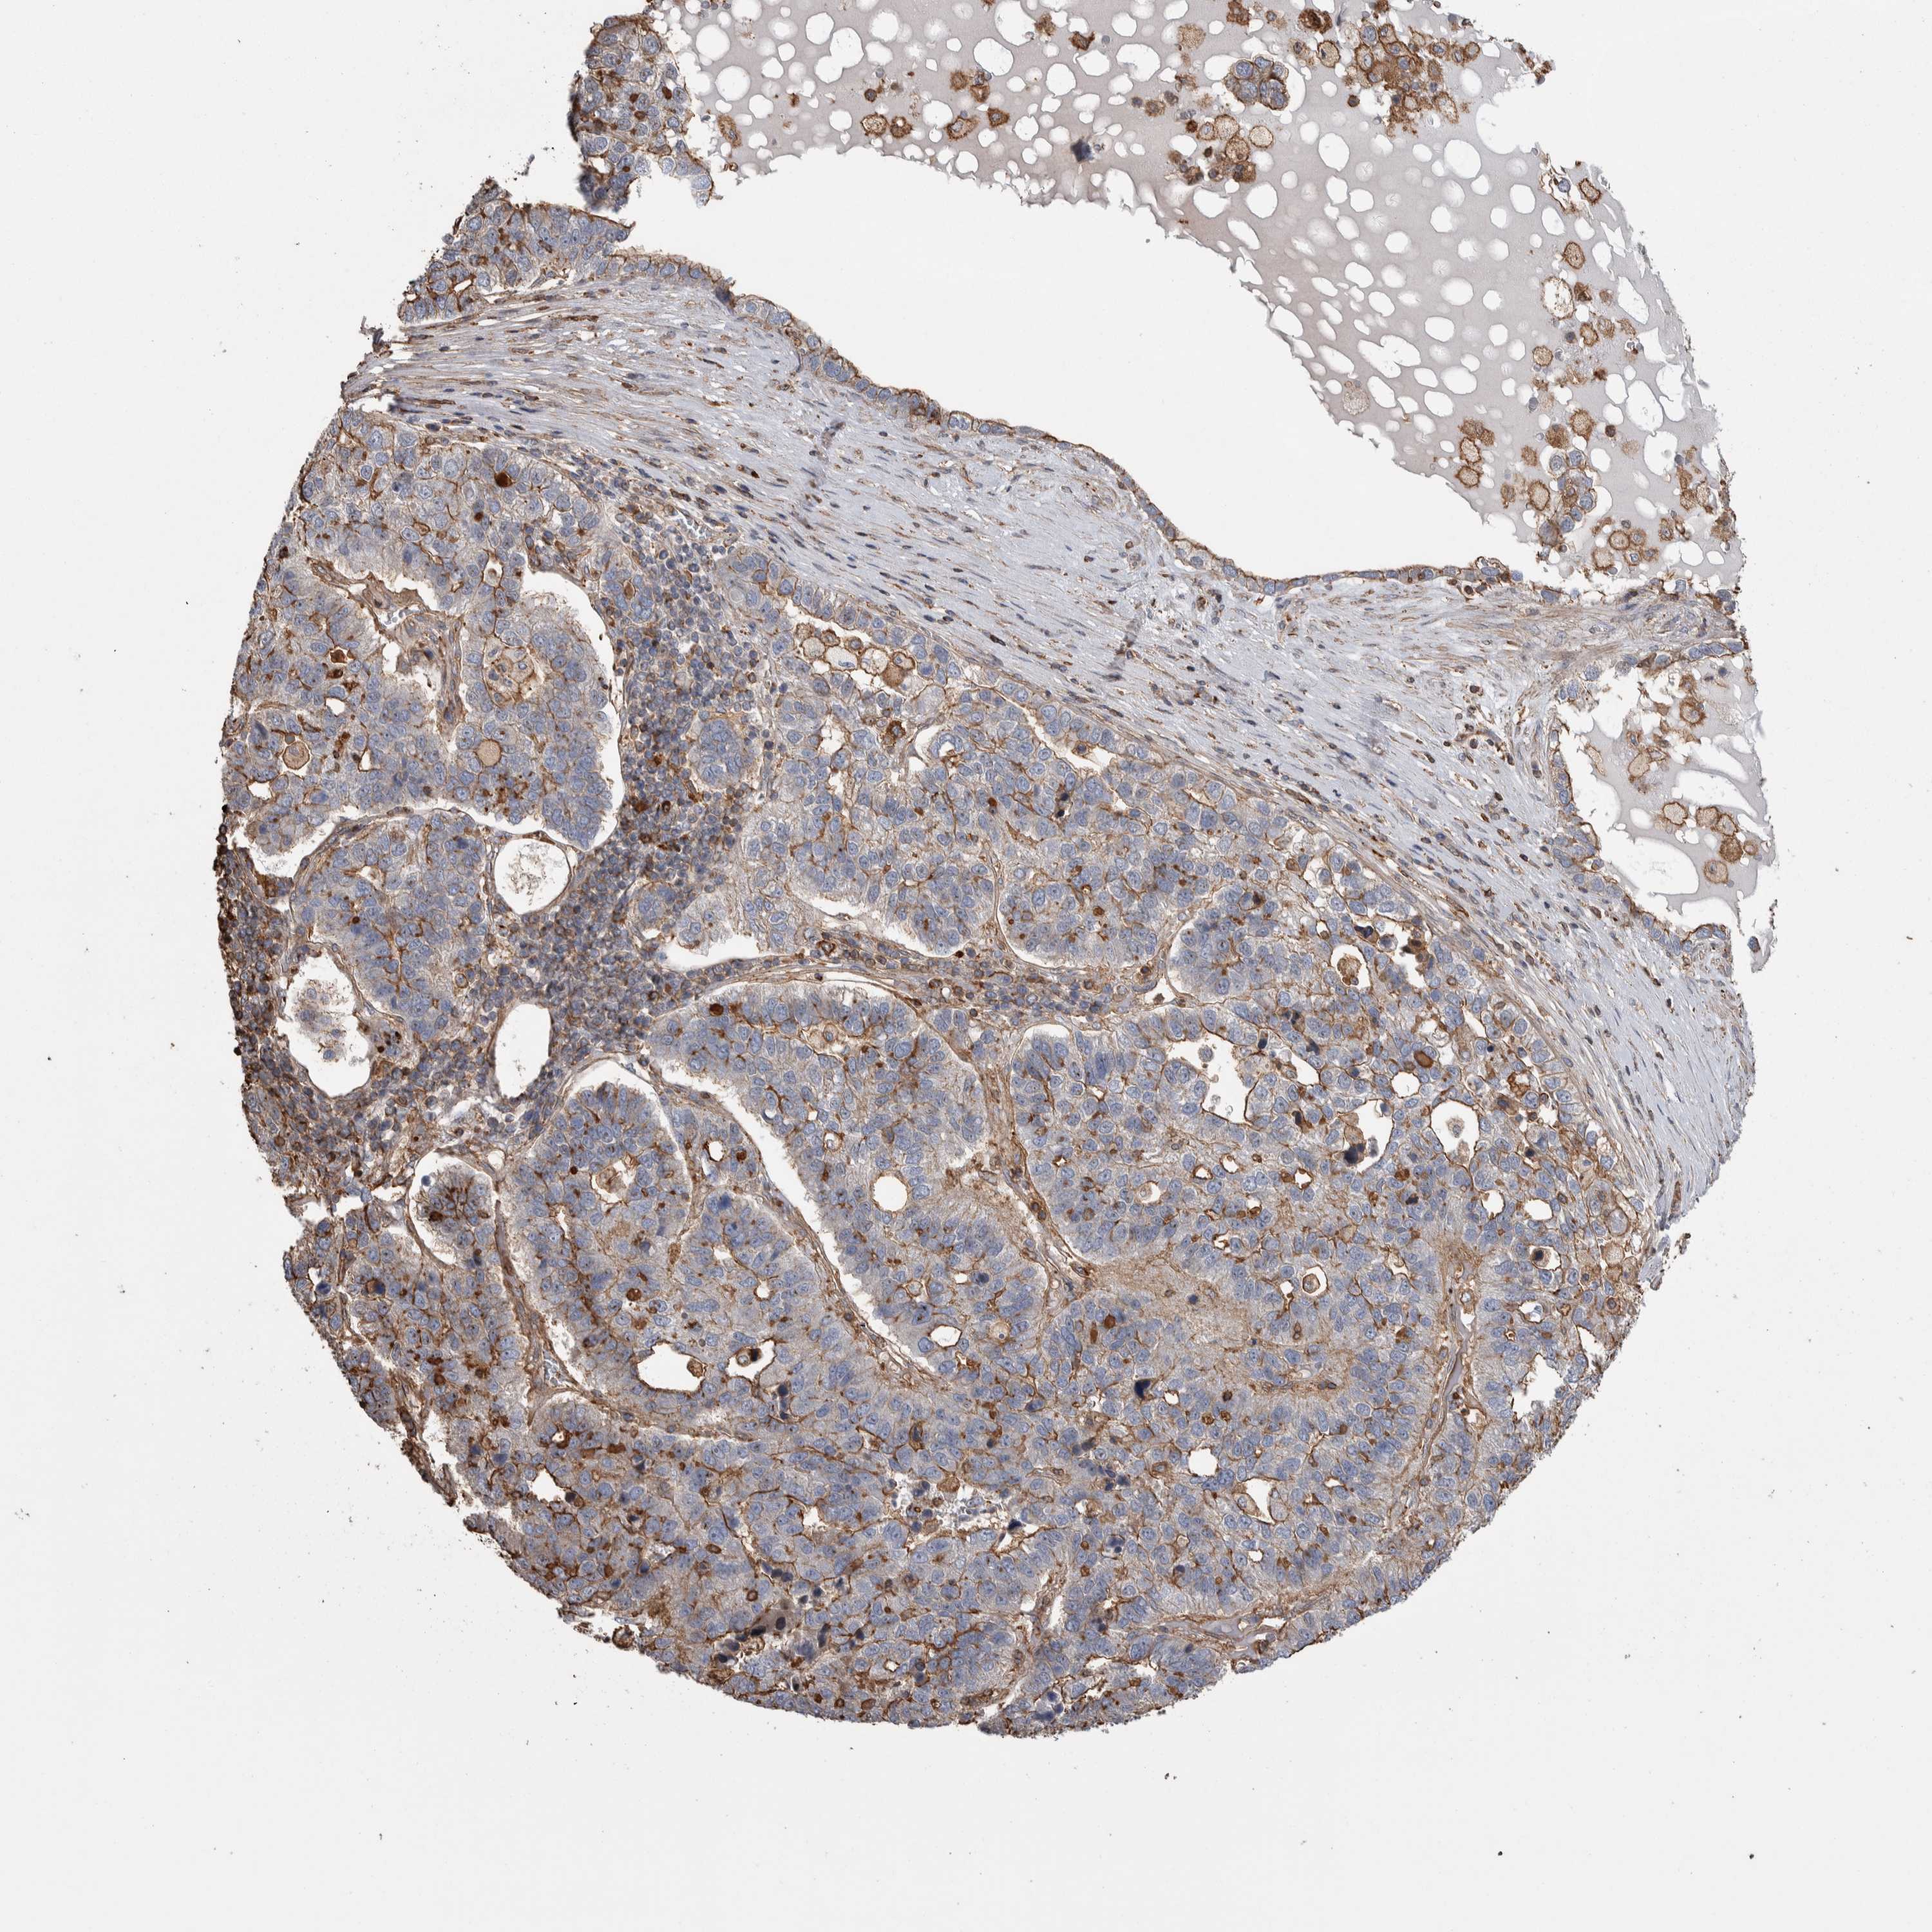

PANCREATIC CANCER - Protein expressioni

A mouse-over function shows sample information and annotation data. Click on an image to view it in a full screen mode. Samples can be filtered based on level of antibody staining by selecting one or several of the following categories: high, medium, low and not detected. The assay and annotation is described here.

Note that samples used for immunohistochemistry by the Human Protein Atlas do not correspond to samples in the TCGA dataset.

Antibody stainingi

Antibody staining in the annotated cell types in the current human tissue is reported as not detected, low, medium, or high, based on conventional immunohistochemistry profiling in selected tissues. This score is based on the combination of the staining intensity and fraction of stained cells.

Each image is clickable and will lead to virtual microscopy that enables deeper exploration of all samples and also displays staining intensity scores, fraction scores and subcellular localization as well as patient and tissue information for each sample.

Antibody HPA023700

Staining

High

Medium

Low

Not detected

Intensity

Strong

Moderate

Weak

Negative

Quantity

>75%

75%-25%

<25%

None

Location

Nuclear

Cytoplasmic/membranous

Cytoplasmic/membranous,nuclear

Adenocarcinoma, NOS